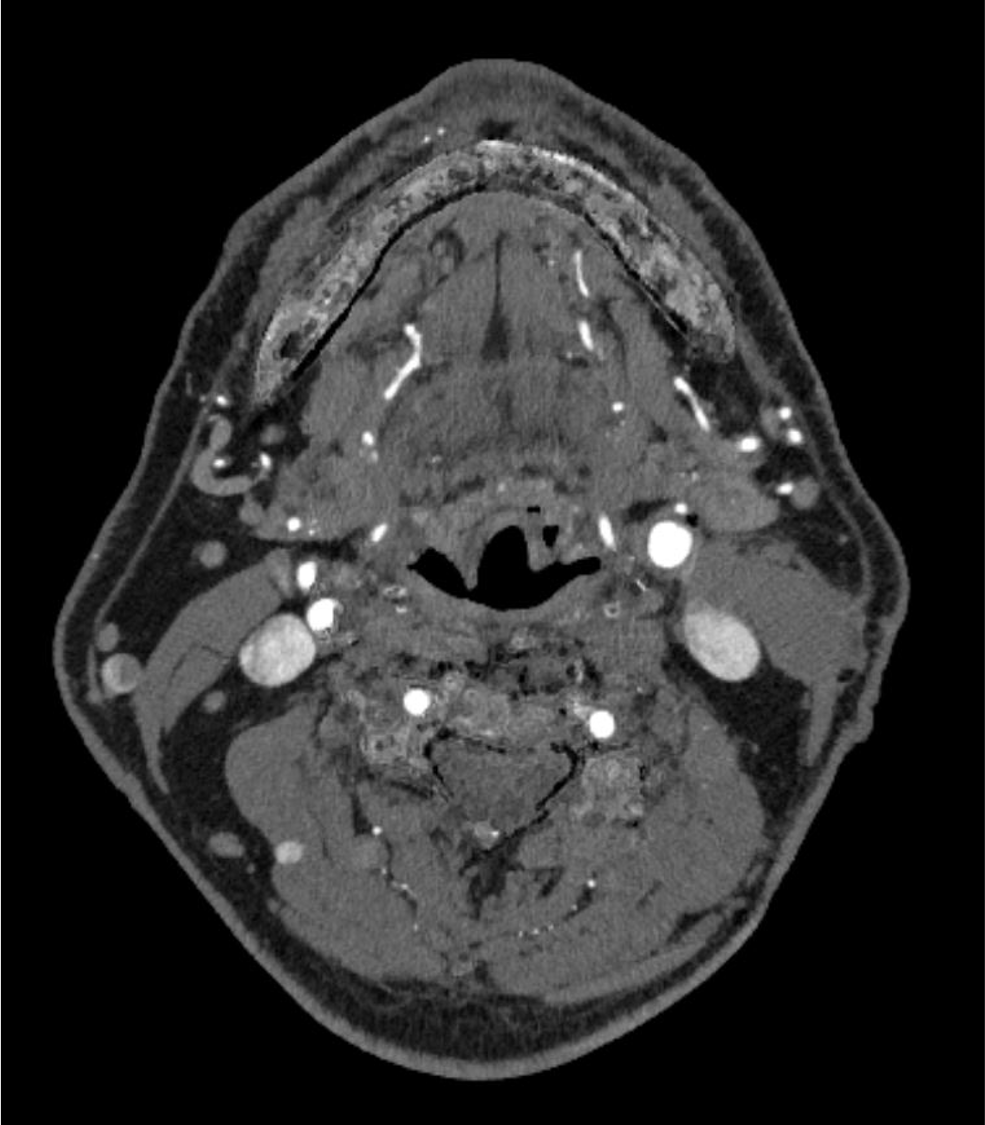

内頸動脈狭窄症において、造影CTはMRIと並んで必須の検査である。MRIが苦手とする石灰化の評価、薄いスライス厚での狭窄率評価が、造影CTでは行いやすい。動脈相での評価が望ましく、血管内と血管外の境界が可能な限りシャープである方が、狭窄率の評価が行いやすい。

CT技術や撮像プロトコル設定について

Virtual Monoenergetic Imageで高エネルギー側の表示をすることで、金属アーチファクトを低減できたり、今回の症例のように、Iodine mapを用いることでヨード濃度を推定することができたり、Purelumen画像でCaなどの石灰化を除去することで、内腔の表示をより明瞭化する技術がある。シャープネスの高い動脈相の画像が望ましく、ヨード量は600mgI/kgは維持できるように気をつけている。